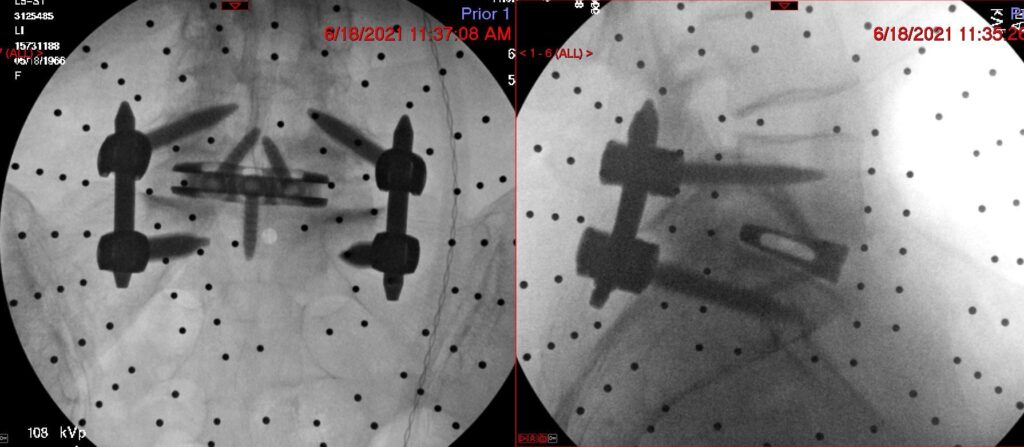

Anterior Lumbar Interbody Fusion